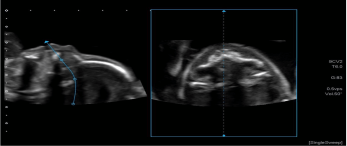

4.智能传感器3D成像(Smart Sensor 3D) :该技术在于弥补常规容积探头成像范围的不足,容积图像范围更大。Smart Sensor 3D可以与其他成像技术联用,包括超微血流成像iSMI、超声造影CHI,Fly Thru,剪切波弹性成像SWE等,

5. 仿内镜导航技术Fly Thru:实时动态显示人体内液性的管腔、体腔和血管内部的立体结构,帮助临床对体内的微小病变更好的发现和治疗,应用于容积探头或Smart Sensor 3D模式。